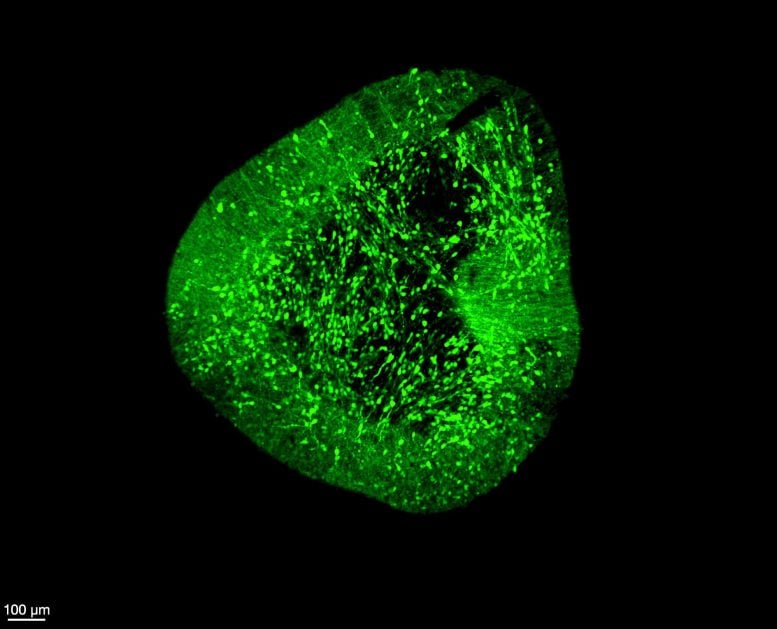

A groundbreaking brain atlas maps nearly 680,000 cells to reveal how the human brain develops at the single-cell level. The discovery could transform Parkinson’s research by setting new standards for building accurate lab-grown neurons. Researchers at Duke-NUS Medical School, together with international collaborators, have produced one of the most detailed single-cell maps of the developing […]Biology,Brain,Duke-NUS Medical School,Neuroscience,Parkinson’s Disease#Brain #Map #Changing #Parkinsons #Disease1770493875